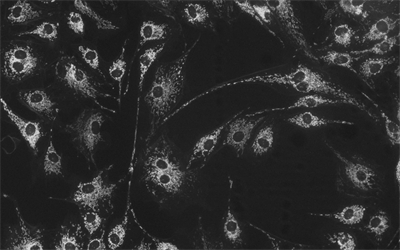

MHS700-MC(黑白)相機(jī)采用Sony Exmor CMOS芯片,針對傳感器固有的熱噪聲,專門設(shè)計了高效制冷模塊使得相機(jī)傳感器的工作溫度比環(huán)境溫度低達(dá)-40度,大大降低了圖像噪聲,保證了圖像質(zhì)量的獲取。

相機(jī)可用于弱光或熒光圖像的拍攝與分析,主要應(yīng)用于以下領(lǐng)域顯微拍攝:

• 明場顯微鏡;

• 暗場,微分干涉 (DIC) 顯微鏡;

• 活體細(xì)胞成像,細(xì)胞或組織病理學(xué)檢測,細(xì)胞學(xué);

• 缺陷分析,半導(dǎo)體檢測,精密測量;

• 微光熒光成像,GFP 或 RFP 分析,熒光原位雜交(FISH);

• 熒光共振能量轉(zhuǎn)移顯微鏡,全內(nèi)反射熒光顯微鏡,實時共聚焦顯微鏡,失效性分析,天體照相。